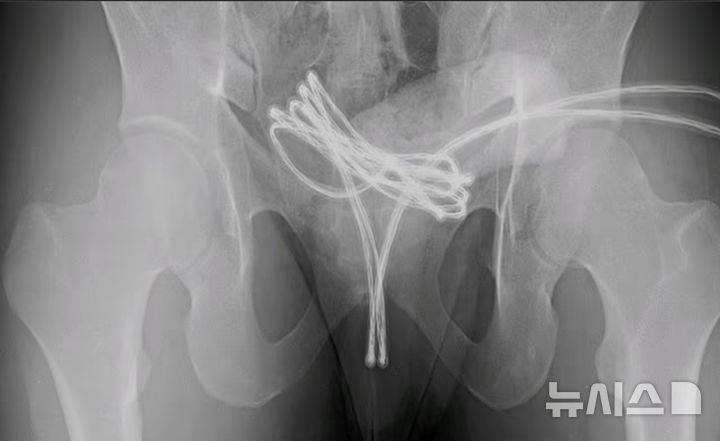

요도에서 나온 USB 케이블…美 남성 스스로 넣은 이유는?

강세훈기자2025.06.15 05:00:00